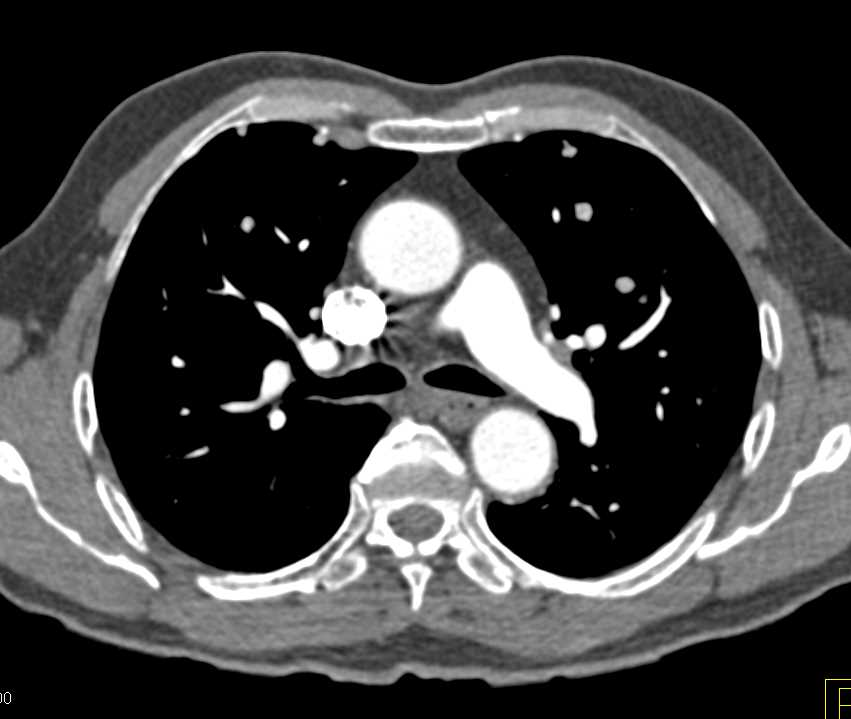

Lymphoma with Adrenal and Liver and Lung Involvement